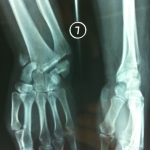

Fangs can penetrate the joint and contaminate it, damaging the cartilage, cutting into the external cortex and even fracturing, particularly in the digital segments.

The extent of skin involvement makes aseptic closure sometimes impossible. Closure should not be carried out under tension, or with economical trimming.